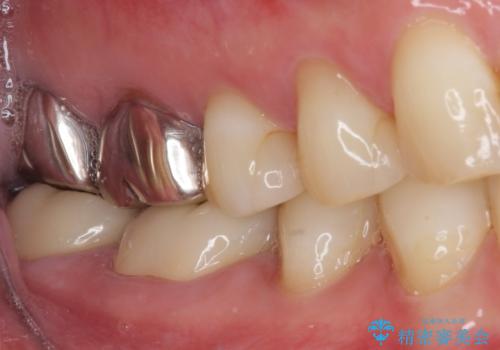

- 以前、職場近くで夜遅くまで治療していた医院で装着した奥歯のクラウンが、壊れたり汚れたりしていることを気にして来院された患者様です。

以前は安価であったことからハイブリッドクラウンを選択されたそうですが、すぐに具合が悪くなってしまったので、今回はオールセラミッククラウンにて補綴治療を行うこととしました。

咬合力が強く、土台の歯の高さが低かったたため、より高強度のフルジルコニアクラウンにて補綴治療を行いました。